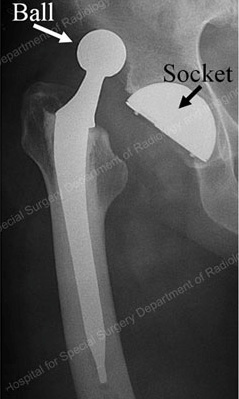

As mentioned above, a hip replacement implant's structure resembles that of the natural hip (a ball and socket). For a hip replacement to function well, the ball must remain inside the socket at all times. Two key factors keep the ball inside the socket: (1) the alignment and fit of the ball and the socket, and (2) forces generated by the strong muscles and ligaments around the hip joint. A hip replacement is designed to have a large range of motion. However, trauma or certain hip positions can force the hip ball out of the socket. This condition is called a dislocated hip or hip dislocation (Figure 2).

Figure 2: X-ray of a dislocated total hip replacement prosthesis showing the ball forced out of the socket